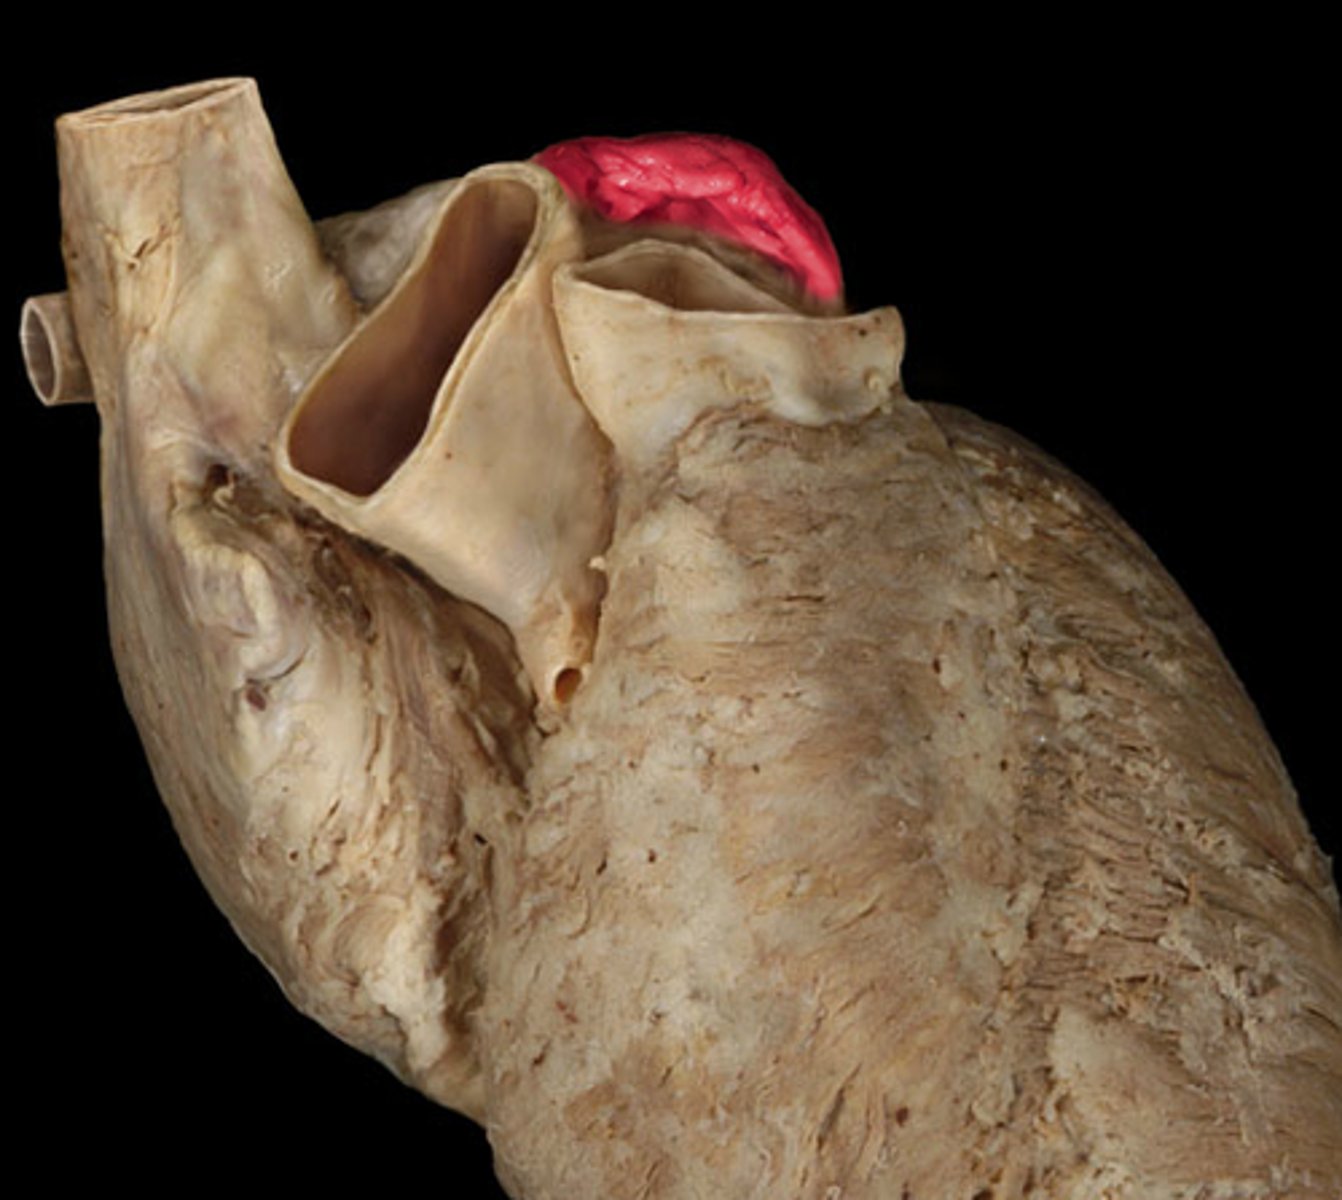

left auricle